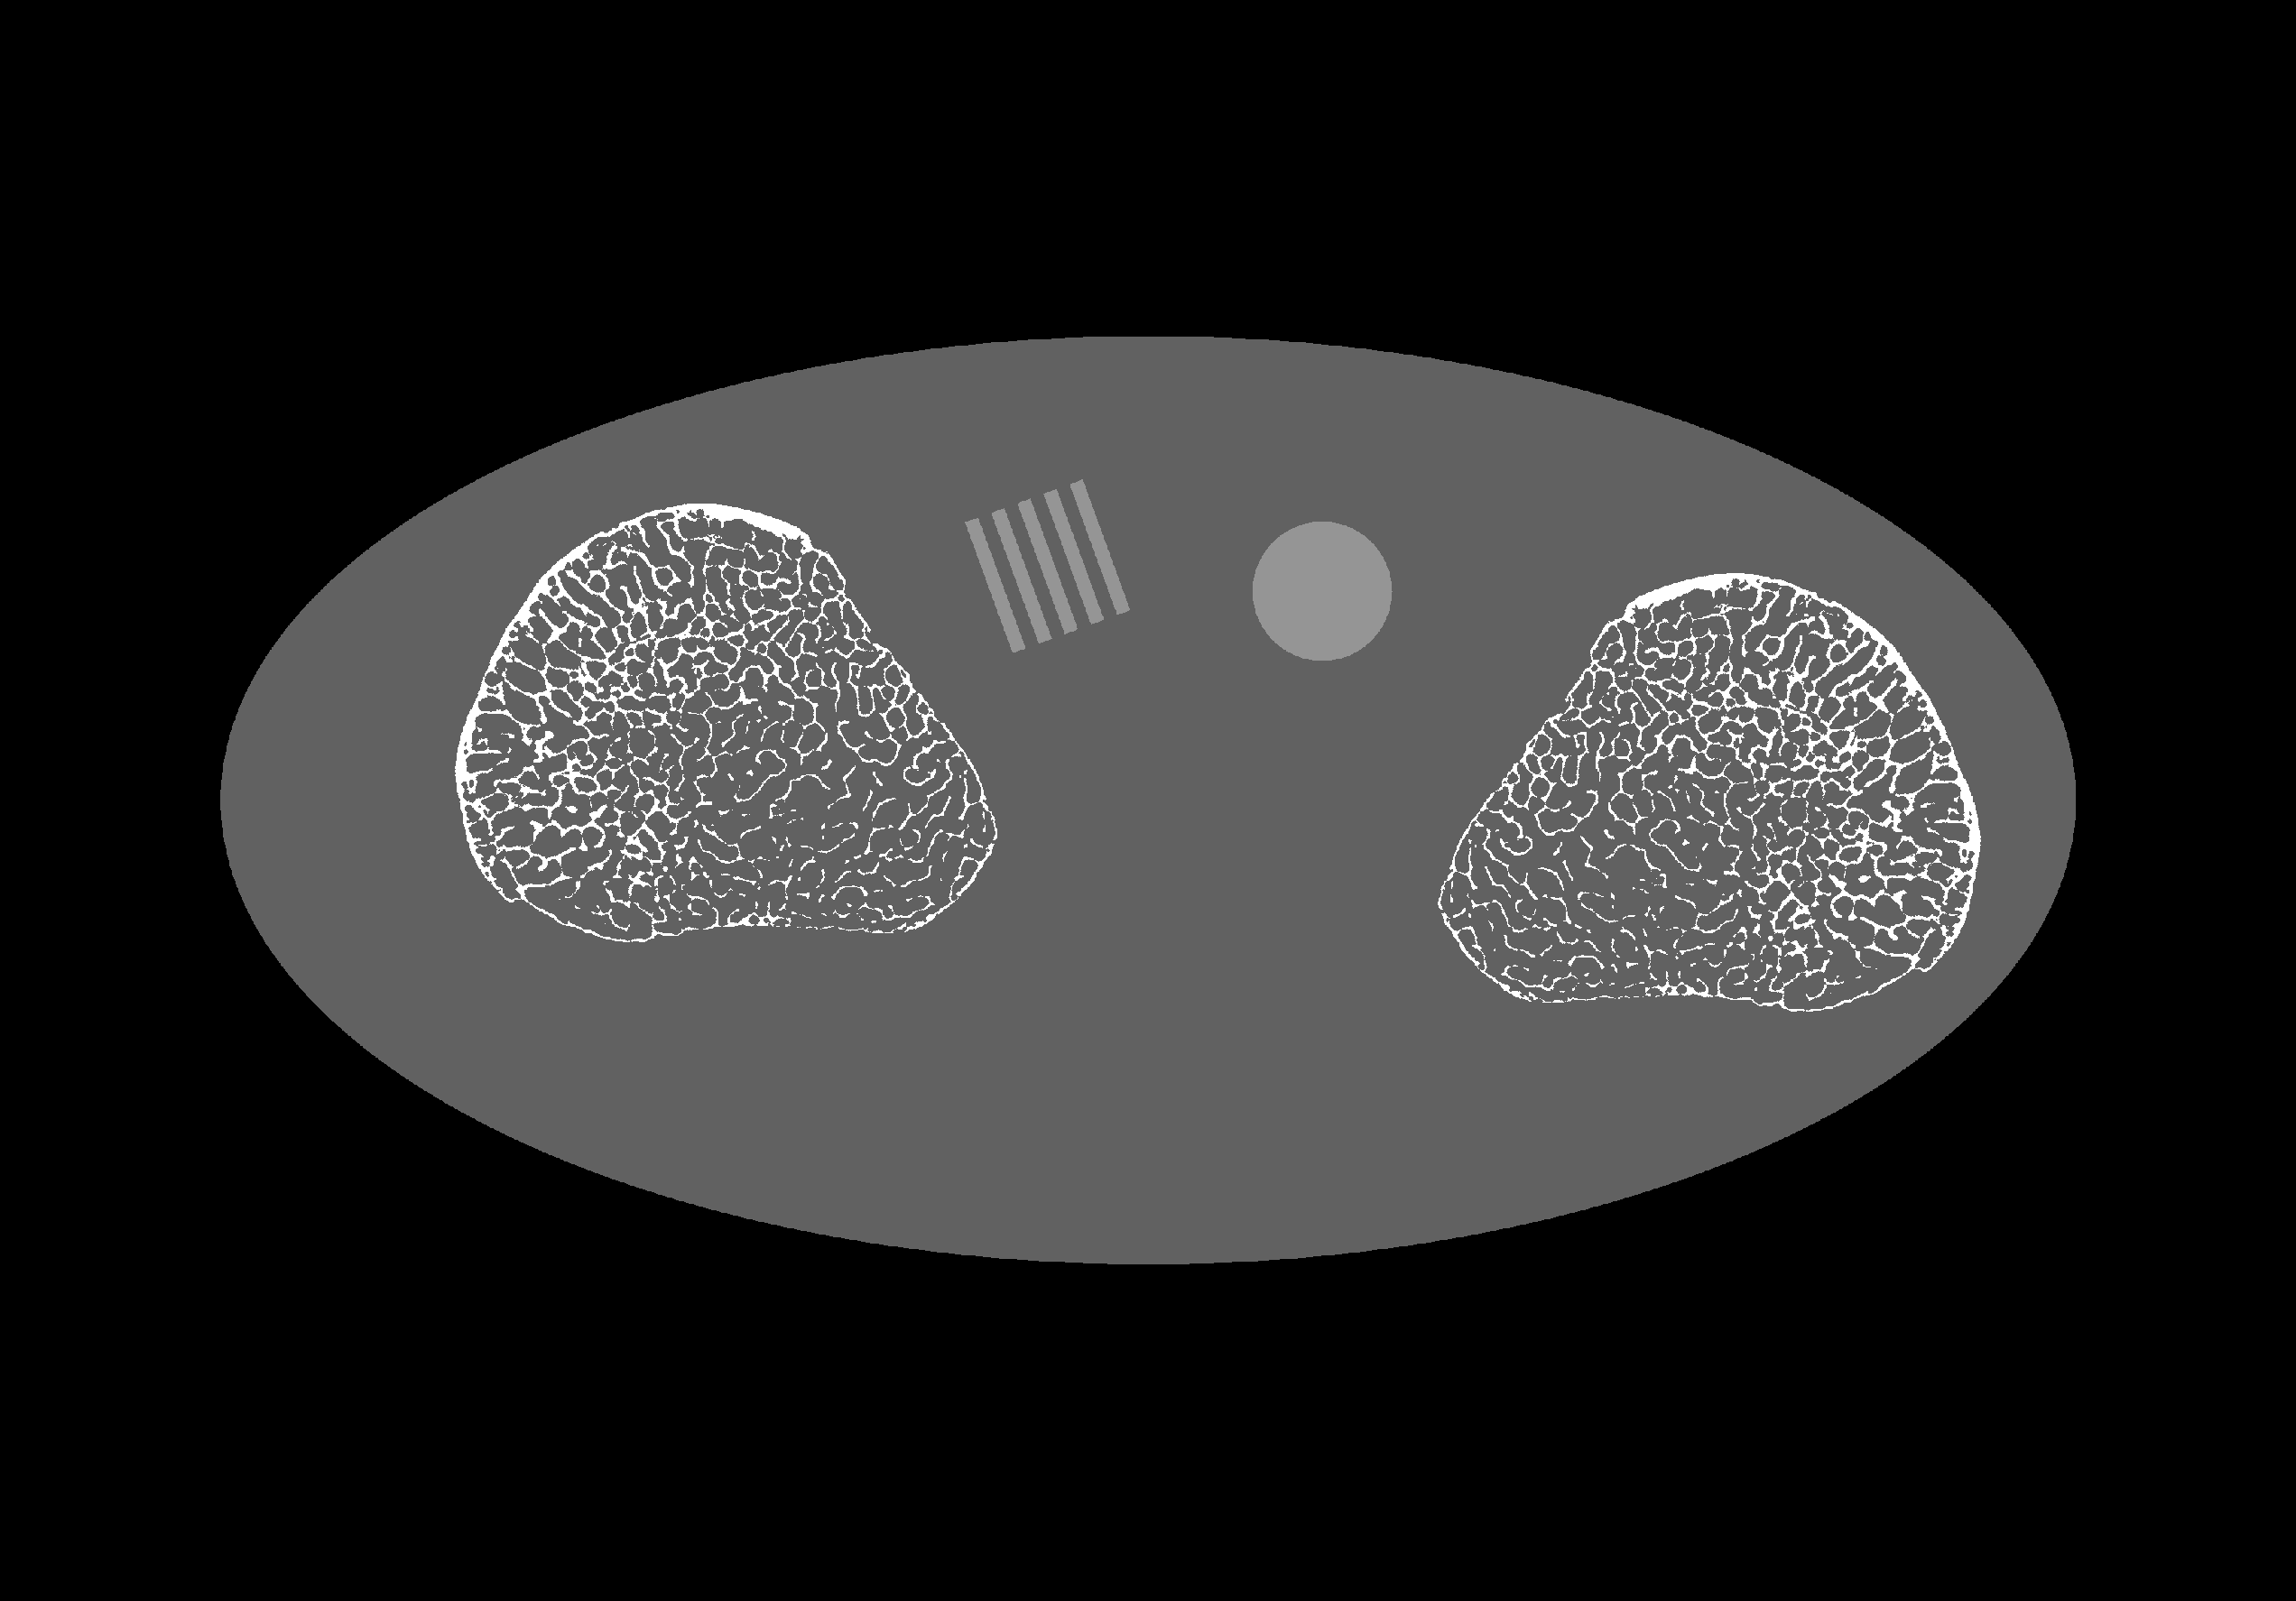

Refer to caption(a)(b)(c) Medial(d) LateralRefer to caption0.0000.0080.0160.0240.0320.0400.0480.056mm-1

Figure 2: Digital extremeties phantom with medial (c) and lateral (d) bones, line pairs (a), and a uniform disc (b).

Data were generated from the digital extremities phantom in Figure 2. Line integrals were generated from a high-resolution truth image (3300×\times2300 image of 30µm voxels) projected onto a one-dimensional detector with 8192 pixels and a 48.5µm pixel pitch. A high-magnification geometry was used, with a source-detector distance of 1200mm, a source-axis distance of 250mm, and an angular spacing of 0.5. These line integrals were downsampled by a factor of 4 to give a pixel pitch of 194µm. Measurements were generated from the downsampled line integrals (l𝑙l) according to:

where I0subscript𝐼0I_{0} is 104superscript10410^{4} photons per pixel, 𝐁ssubscript𝐁𝑠\mathbf{B}_{s} is the focal spot blur operator (we assume there is no detector blur), and the readout-noise standard deviation (σrosubscript𝜎𝑟𝑜\sigma_{ro}) is 3.32 photons. The focal spot was modeled as a 5mm×\times0.8mm rectangle on a 14 anode with the anode-cathode axis parallel to the detector row. The sampling factor (s𝑠s) was equal to 41. (Note that 𝐁sI0subscript𝐁𝑠subscript𝐼0\mathbf{B}_{s}I_{0} is equivalent to 𝐁𝐁\mathbf{B} in (1).) Data were generated using two short scans (short-1 and short-2) spaced 180 degrees apart, and a full scan. The short-1 scan placed the medial bone (Figure 2c) predominately on the anode side, and the lateral bone (2d) predominately on the cathode side. The reverse is true for the short-2 scan.